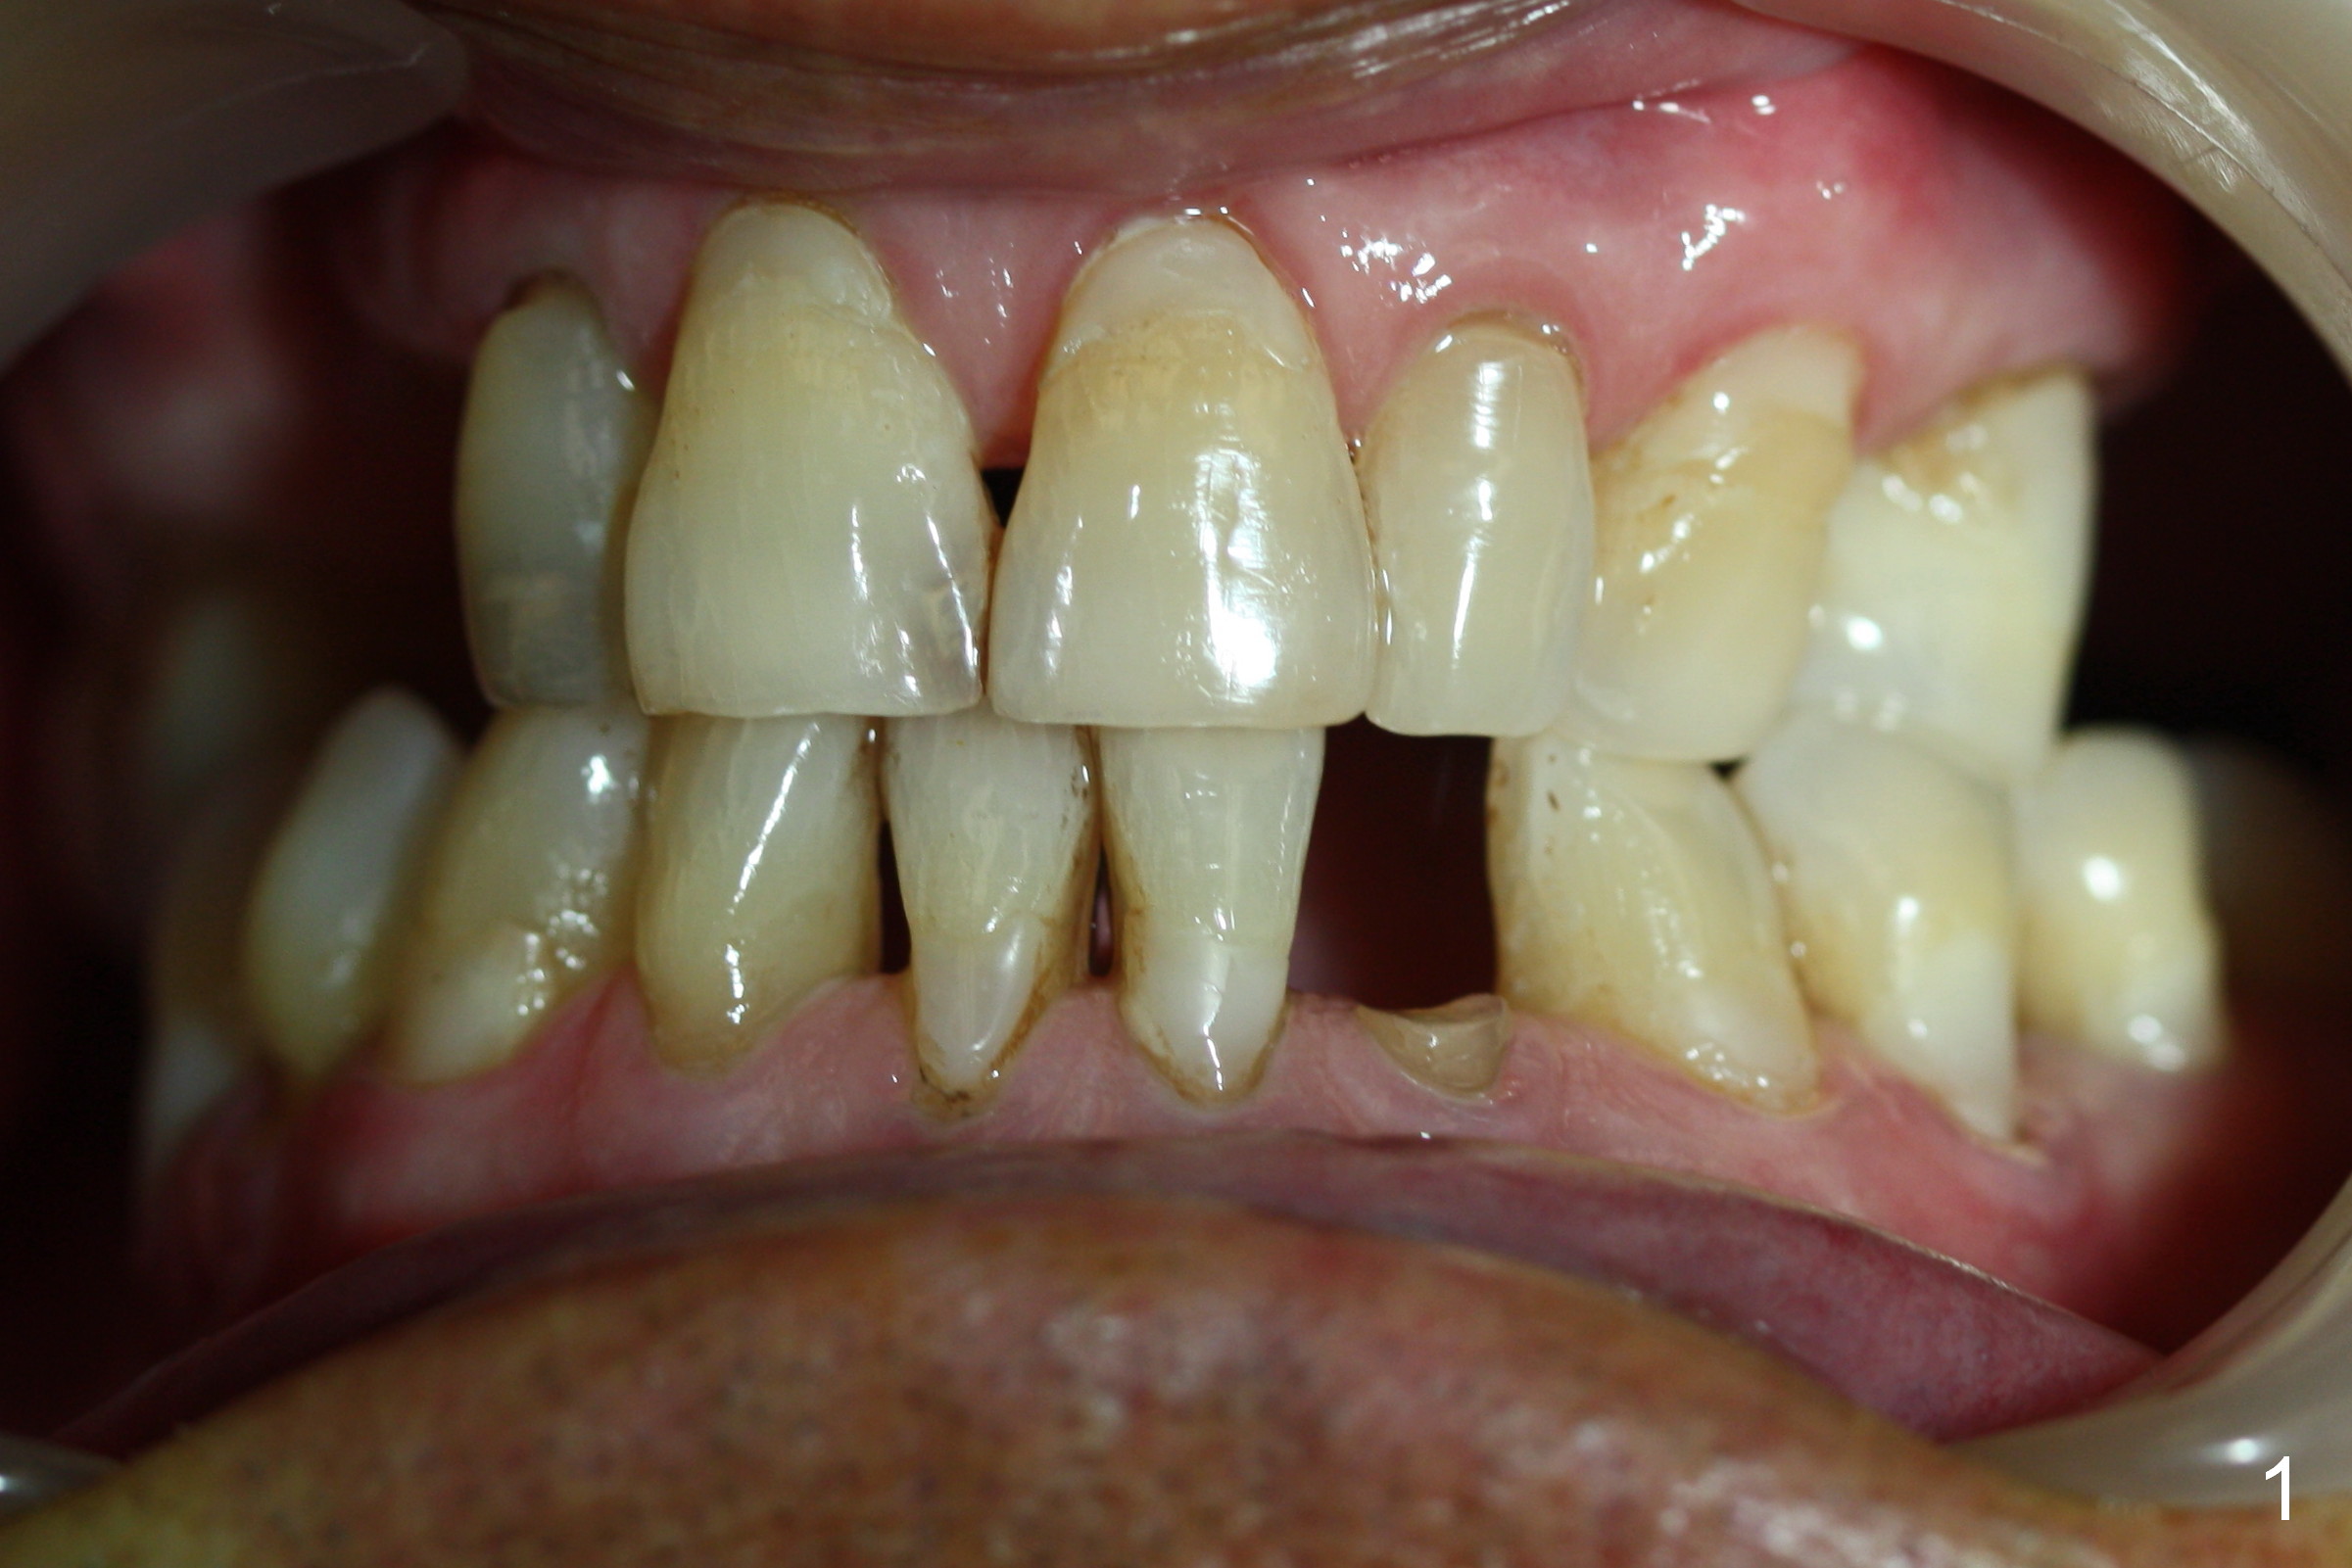

A 74-year-old man has several missing teeth (Fig.1). His 1st goal is to replace the lower left lateral incisor (Fig.2). The residual root has an apical lesion (Fig.3 *). To describe intraop findings, a CT image of a different patient is used (Fig.4 coronal section; B: buccal; L: lingual). After extraction, the buccal plate is found to be thin and low (Fig.5 arrowheads). A 1.5 mm pilot drill (Fig.6 red line) is used to initiate osteotomy in the lingual plate of the socket. Once the drill penetrates the lingual plate, the trajectory changes and the depth is 17 mm from the gingival margin (Fig.7). A PA is taken (Fig.8); it appears that the osteotomy can be extended more apically. When the pilot drill extends to 20 mm, there is sudden empty feeling. The lingual plate has perforated (Fig.9). A new osteotomy is established buccally (Fig.10 pink). To avoid buccal plate perforation, especially in the buccal undercut area (>), the coronal end of the drill has to be tilted buccally (<--). An angled abutment (3x20 mm, 15°) is placed (Fig.11,12). The abutment is modified (Fig.13,14) to accommodate an immediate provisional (Fig.15,16 P). Perio dressing is to be applied to prevent the bone graft from getting dislodged buccally (Fig.15). The dressing is in place 7 days postop (Fig.17).